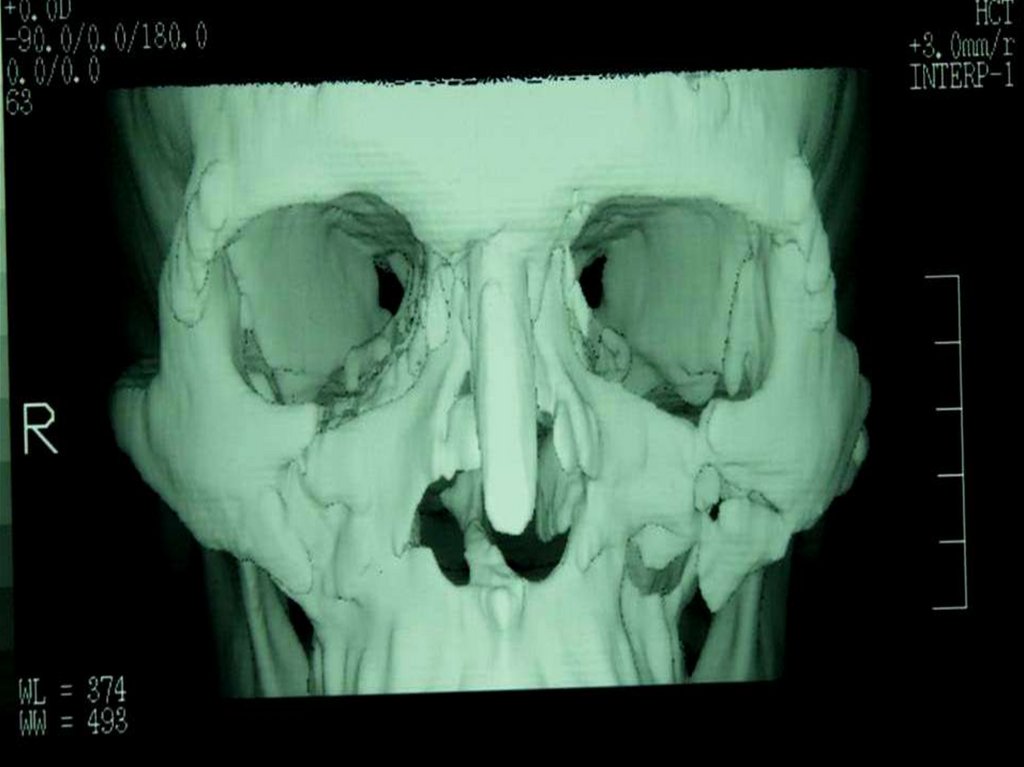

При костной пластике

необходим анализ

дефекта и четкое

планирование его

устранения.

При помощи

математического анализа

выработана множество

методики расчета

размеров требуемого

трансплантата и

обоснование способов

его фиксации.